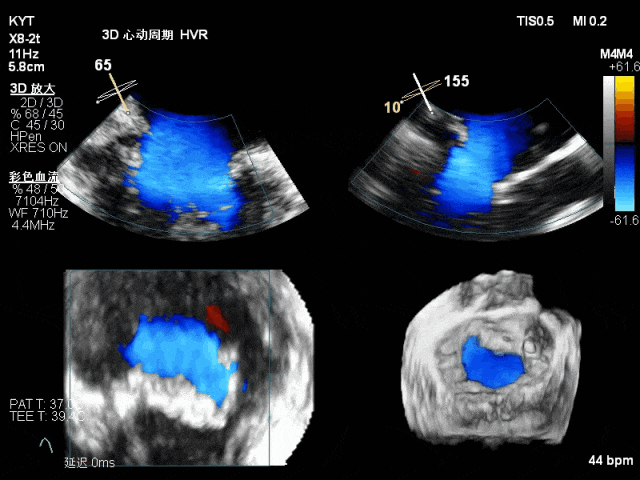

放置第一枚NTR夹合器后的TEE 3D影像,瓣叶脱垂明显改善